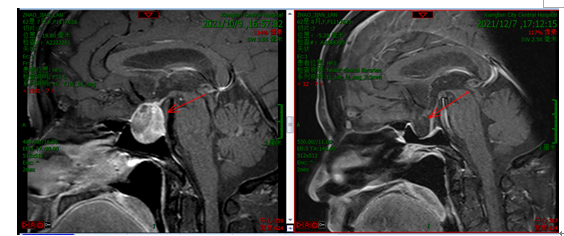

10 月 12 日,由神经外科副主任杨佳宁主刀、副主任医师彭龙组成的手术团队历时 4 小时,为患者顺利完成手术。术后,患者无感染、无脑脊液漏、无垂体功能低下,复查头部 CT 及 MR 提示肿瘤切除满意,术后 7 天患者出院。目前,随访 2 个月仍无垂体功能低下及无脑脊液漏,患者生活质量得到极大改善。